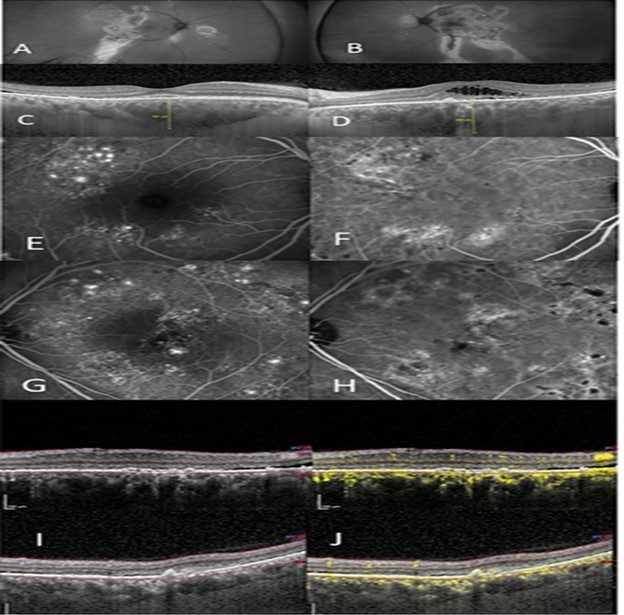

Figure 2.(A) right eye show autofluorescent discontinuity with peripheral tracks. (B) left eye show similar changes however central changes are present. (C), (D) OCT/EDI shows pachychoroid, pachy vessels, varying degrees of subretinal and intraretinal fluid, right eye (C), left eye (D). (E) IVFA right eye shows non-specific extrafoveal occult leakage. (F) ICG right eye with ICG hyperfluorescence and corresponding leakage. (G) IVFA leakage, left eye with several focal leaks amongst wider areas of non-focal leakage. (H) ICG shows diffuse hyperfluorescence corresponding to IVFA leakage. (I) OCT shows two images of the left macula with the “double layer sign” superior and a visible Type 2 neovascular membrane inferior, thickened choroid, and subretinal fluid and (J) with corresponding OCTA scans showing neovascularization.

(A) right eye show autofluorescent discontinuity with peripheral tracks. (B) left eye show similar changes however central changes are present. (C), (D) OCT/EDI shows pachychoroid, pachy vessels, varying degrees of subretinal and intraretinal fluid, right eye (C), left eye (D). (E) IVFA right eye shows non-specific extrafoveal occult leakage. (F) ICG right eye with ICG hyperfluorescence and corresponding leakage. (G) IVFA leakage, left eye with several focal leaks amongst wider areas of non-focal leakage. (H) ICG shows diffuse hyperfluorescence corresponding to IVFA leakage. (I) OCT shows two images of the left macula with the “double layer sign” superior and a visible Type 2 neovascular membrane inferior, thickened choroid, and subretinal fluid and (J) with corresponding OCTA scans showing neovascularization.

Figure 2 outlines a 52 year old Latino male, previously treated unsuccessfully with eplerenone (Inspra) and multiple anti-VEGF injections in both eyes. He was referred with the diagnosis of Exudative ARMD with a possible CSCR component due to his gender and age. He had chronic exudation, left eye greater than right eye, with macular atrophy left eye and subsequent vision loss. Autofluorescence of each eye reveal prominent peripheral discontinuity with classic gravitational tracks. Additionally, central changes are present in the left eye consistent with the macular atrophy and vision loss. IVFA of both eyes showed widespread extrafoveal exudation with areas of non-specific occult leakage as well as focal leaks. ICG hyperfluorescence shows diffuse choroidal leakage in both eyes. OCT showed a thickened choroid and pachyvessels with the OCTA revealing areas of “double-layer” sign. This patient had simultaneous Group 1 and Group 2a diagnoses.